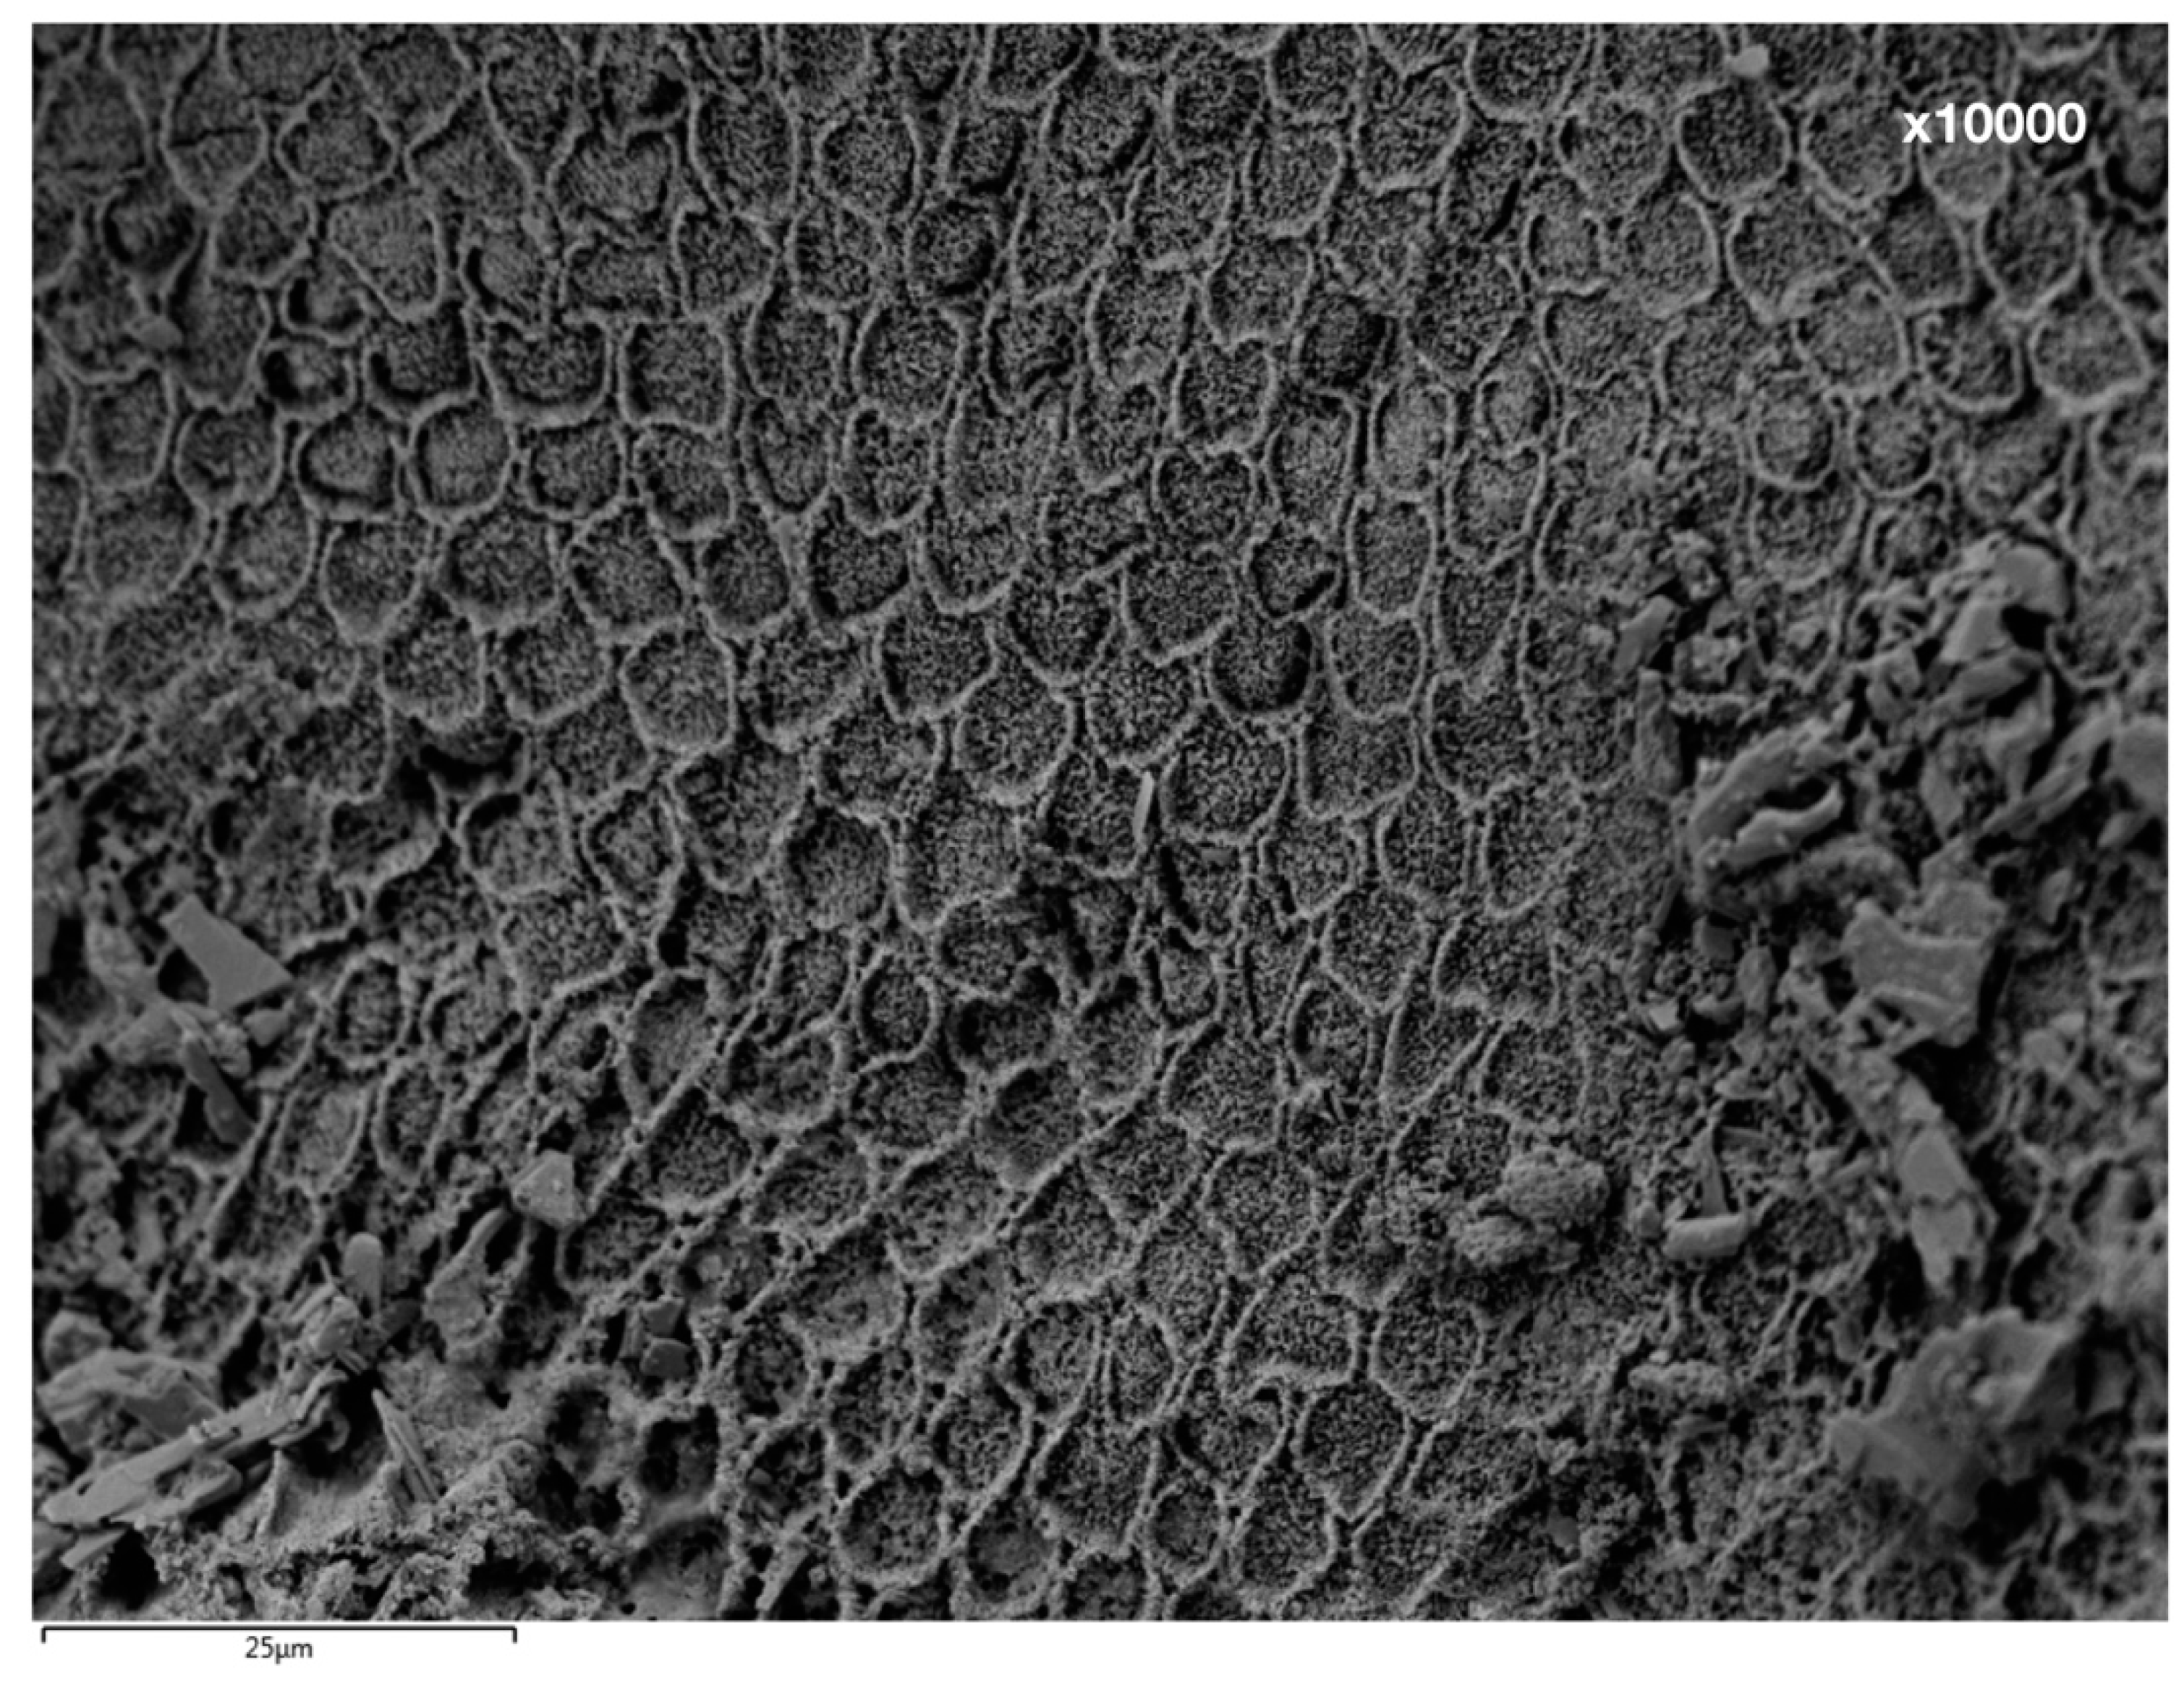

2.3. Scanning Electron Microscopic (SEM) Analysis